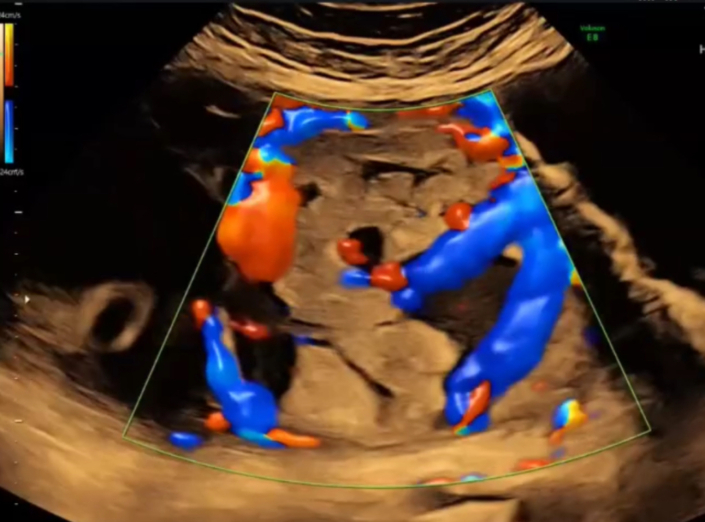

Most women do not have clear symptoms before delivery. However, doctors may suspect PAS based on a review of risk factors and examination using ultrasound (high-frequency sound waves). Typical findings may include the absence of the hypoechoic zone (a clear layer normally seen between the placenta and the uterus), the presence of lacunae (irregular blood-filled spaces) within the placenta, and the placental tissue extending beyond the normal uterine border.